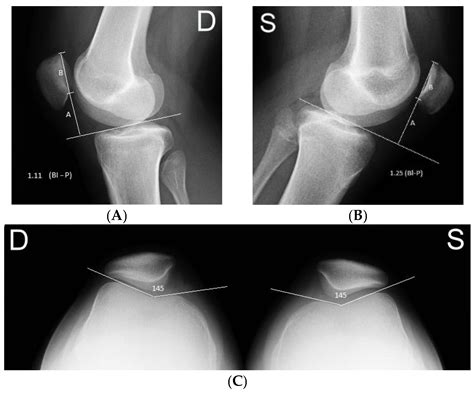

• Imaging Tests: X-rays, MRI, or CT scans to visualize the patella and surrounding structures. These tests can help identify any anatomical abnormalities or soft tissue injuries.